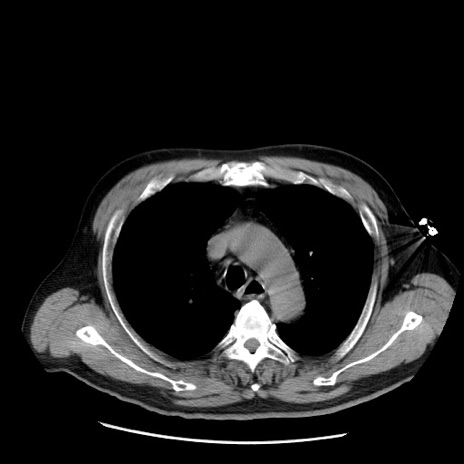

症例20(横断像)

【症例】 60歳代男性

【主訴】 腹部膨満、嘔吐

【現病歴】5日前頃より倦怠感を認め食事量減少し4日前の朝嘔吐、食事摂取困難となった。 3日前近医受診し点滴施行され整腸剤などを処方された。 当日他院を受診し、腹部膨満著明、炎症反応の上昇(CRP10.8、WBC11200)あり、紹介受診となる。

【身体所見】 意識JCS1 受け答えがはっきりしないBP 111/57mHg、 P 67bpm、、BT35.2°C、SpO2 97%(RA)、 腹部:膨隆、打診で鼓音あり、全体的に圧痛有り、腸蠕動音(-)、反跳痛ははっきりせず。

【データ】WBC 11400、CRP 14.20